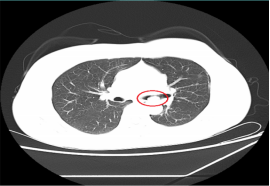

近日,一位患支气管肿瘤患者到我院呼吸内科治疗,检查时,其肿瘤几乎已经完全堵塞气管管腔,若不及时手术,随时可能发生呼吸衰竭。

情况危急,医生立即为其抽取动脉血化验并给予高流量吸氧等,但患者呼吸困难的症状缓解不明显,必须及时将肿瘤切除。“如果按照传统的手术方式,需将患者气管切开,组织损伤性高、流血量多。由于患者肿瘤贴近降主动脉,切除过程中将伴有大出血的风险。”刘碧翠说,随着我院内镜技术的发展,对于这样的重症患者,可以利用呼吸内镜迅速切除肿瘤,清理气道内局部的坏死组织、分泌物并予以止血处理。

科室介入团队经过精心准备后,立刻为患者实施内镜介入手术,将气道内肿物切除干净。手术仅用时2小时,患者没有发生大出血,很快便恢复出院。此次手术的成功开展,充分体现了呼吸内科对此类疑难危重气道疾病患者的救治能力。